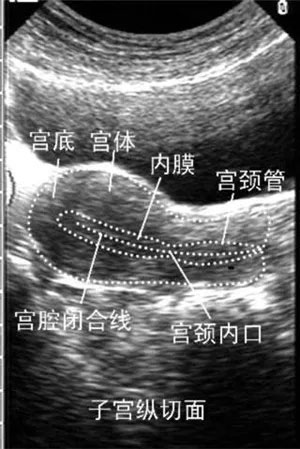

專家指出:導(dǎo)致試管嬰兒治療失敗的原因有很多,其中子宮內(nèi)膜好壞對于試管嬰兒胚胎移植著床有直接的影響,所以,我們在做俄羅斯試管嬰兒前一定要調(diào)養(yǎng)好自己的子宮內(nèi)膜,多了解一些試管嬰兒知識,這對于提高試管嬰兒的成功率有很大的幫助。